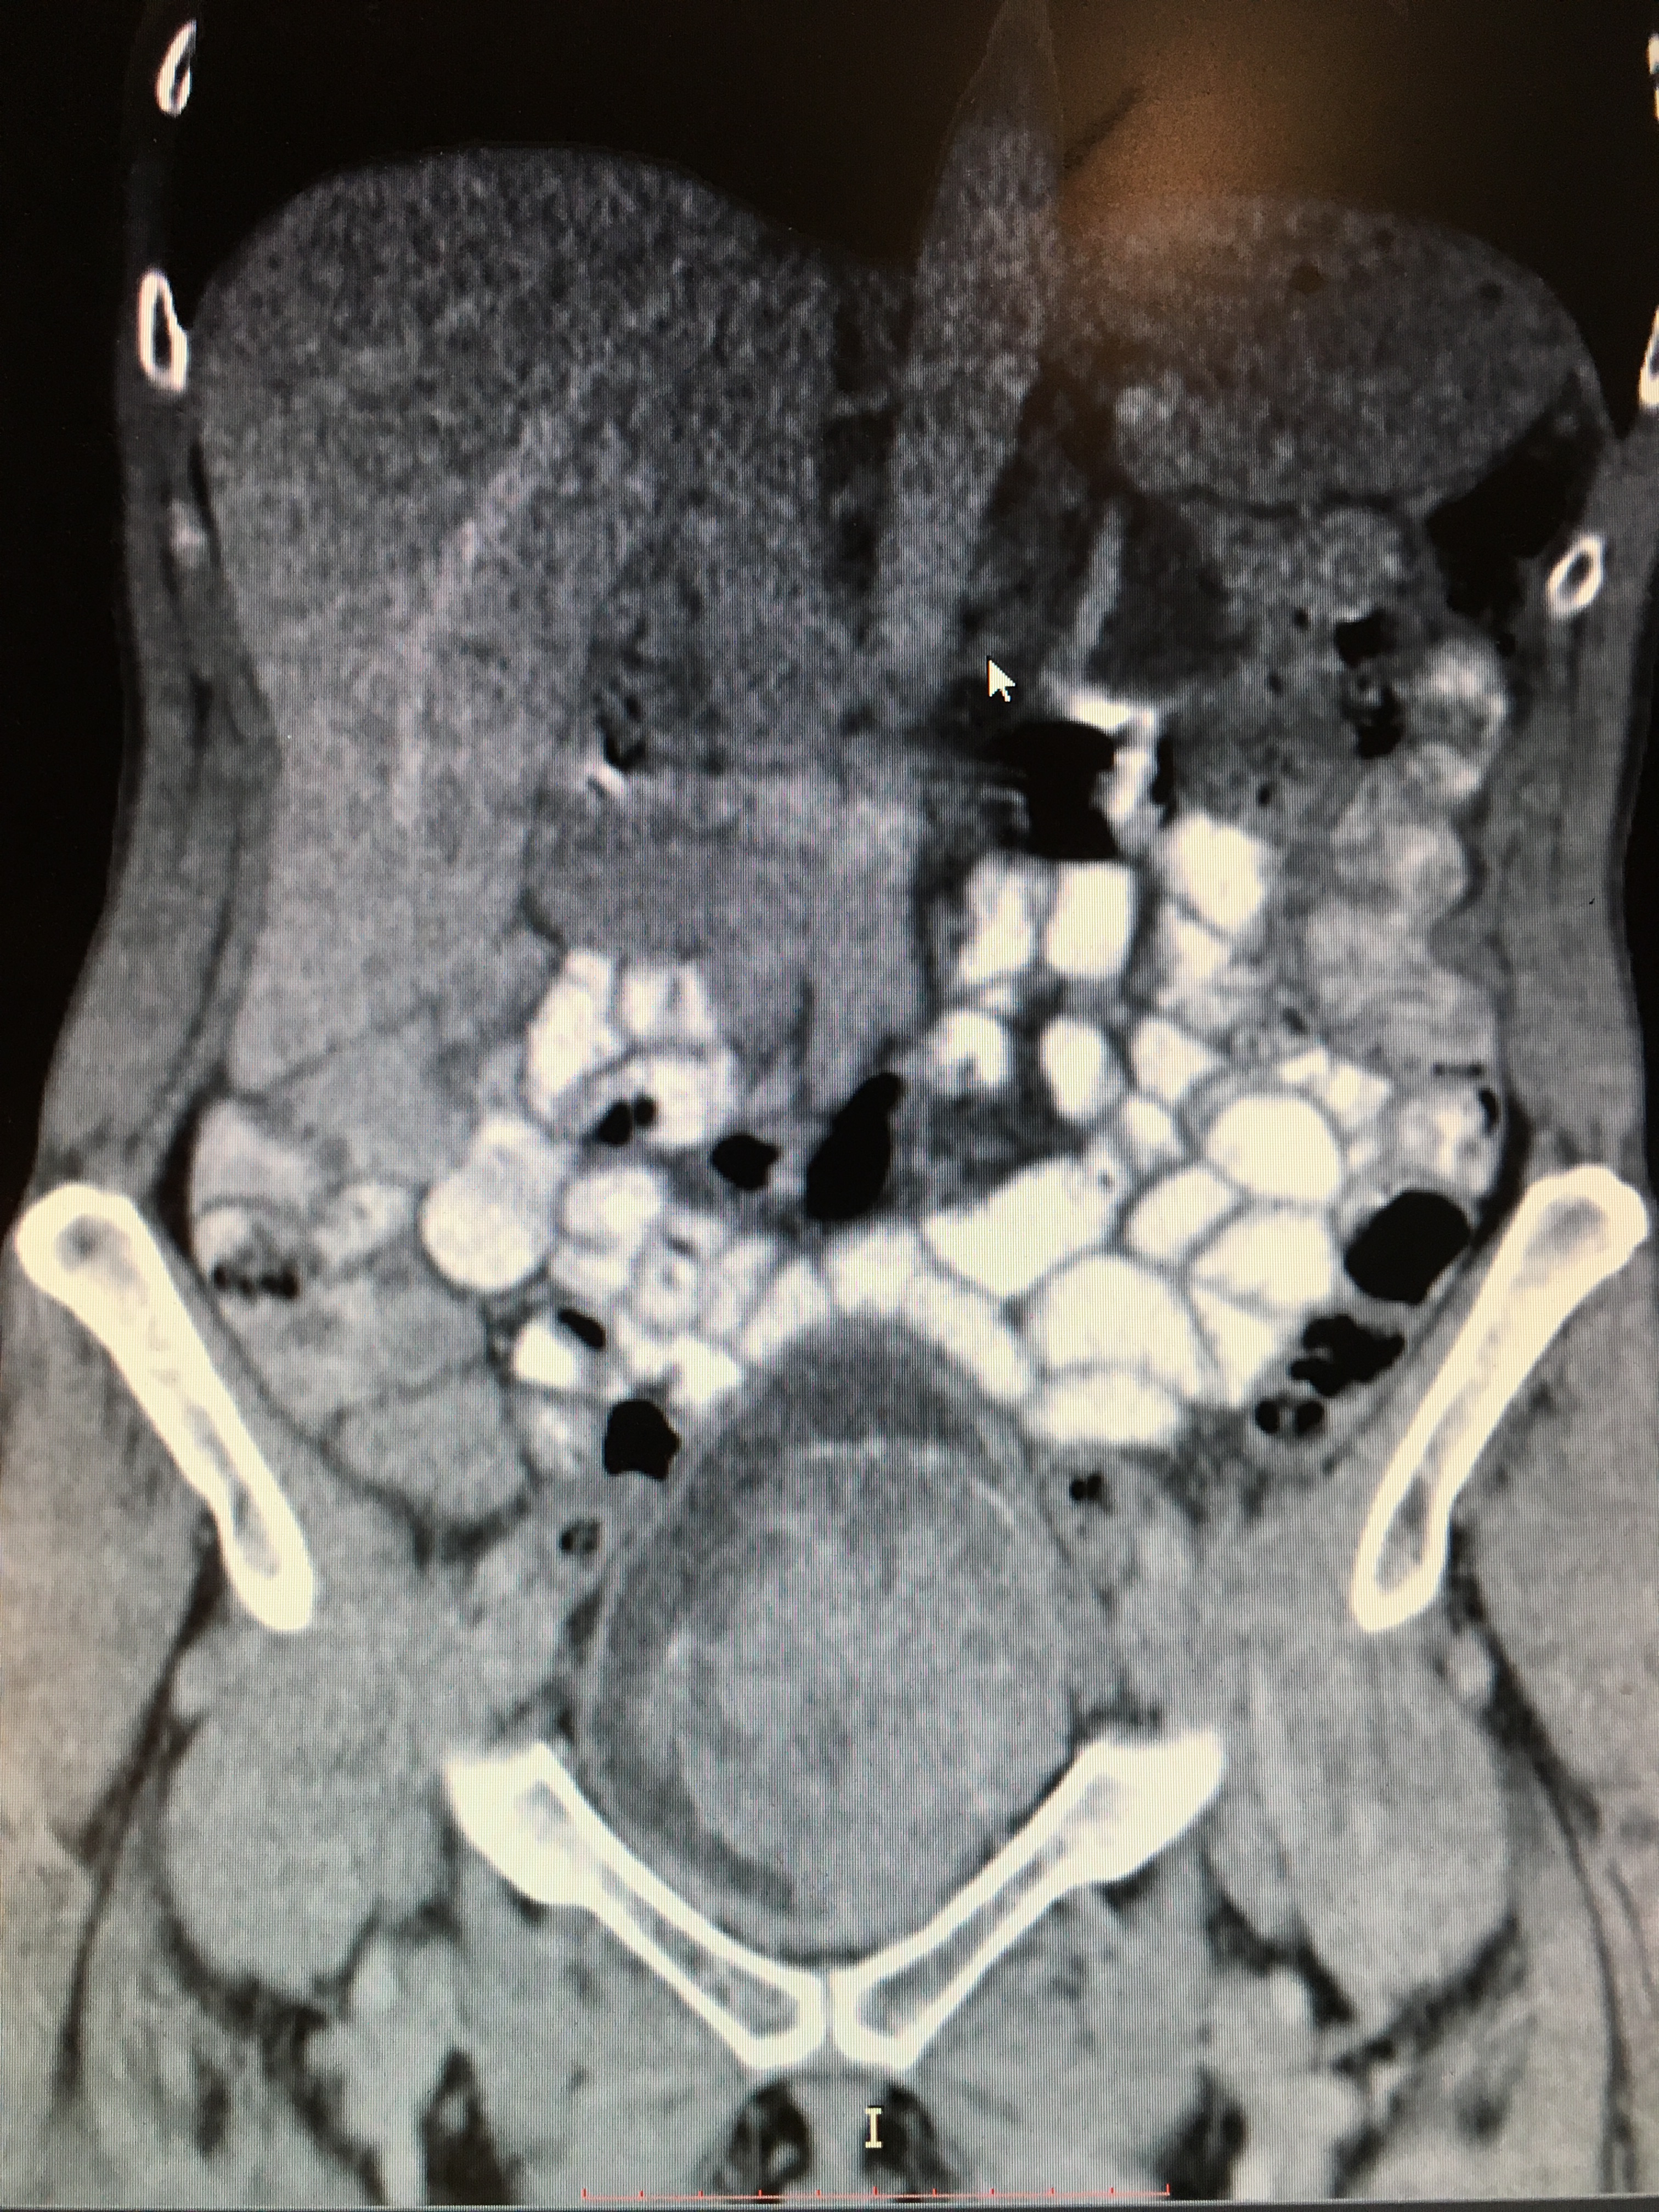

CT vizsgálat

CT (Computer Tomográfia) vizsgálatot általában kontrasztanyaggal és akkor végzünk, ha felmerül, hogy a hólyagdaganat már egy előrehaladottabb állapotot elért. A CT vizsgálat elkészült képeiből információt nyerhetünk a hólyag tumor kiterjedéséről, a nyirokcsomók érintettségéről, valamint a távoli áttétekről. Kontrasztanyagos CT vizsgálathoz szükséges a jó vesefunkció.

A kezelés megkezdése előtt szükséges felmérni a daganat stádiumát képalkotó módszerek segítségével. A has-, kismedence- és mellkas CT információt ad arról, hogy a daganat mérete mekkora, hogy van-e áttét és, hogy a vesevezetéke(ke)t elzárta-e. A csontszcintigráfia vizsgálat arról nyilatkozik, hogy a csontokba a daganat adott-e áttétet. Laborvizsgálatokkal (vérvétel) és EKG-val arról tájékozódunk, hogy milyen a beteg általános állapota, képes-e kibírni egy műtéti vagy kemoterápiás kezelést.

Az izominvazív daganatok ellenőrzésekor célunk az, hogy a daganat előrehaladását – helyi kiújulást, méretbeli növekedést, áttétek megjelenését – időben észrevegyük, ezért rendkívül fontos, hogy minden kontroll vizsgálaton jelentkezzünk. A helyi kiújulás a műtét után a betegek 5-15%-át, a távoli áttétek megjelenése pedig körülbelül a felét érinti. Mindezért a kontroll vizsgálatok során a teljes testet át kell néznünk, melyet leggyakrabban CT-vizsgálattal teszünk meg. Mivel a vesefunkció romlása előfordulhat mind műtét után, mind műtét nélkül, ezért fontos, hogy a vesefunkciós paramétereket is rendszeresen ellenőrizzük (ultrahanggal és vérvétellel). Az ellenőrző vizsgálatok kezdetben háromhavonta történnek, stabil betegség esetén (tehát ha nem nő a daganat és nem jelenik meg újabb áttét vagy helyi kiújulás) az ellenőrző vizsgálatokat elég félévente, majd évente elvégezni.